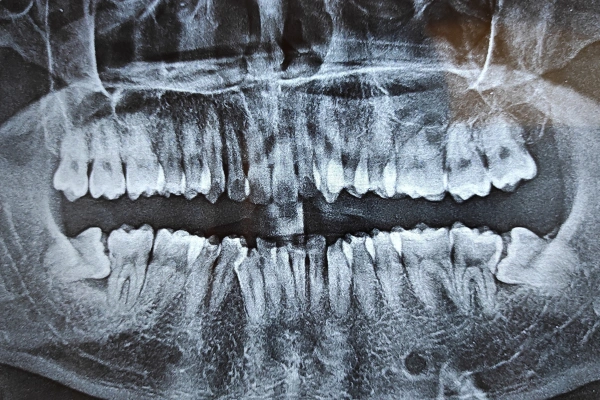

What Is a Wisdom Tooth Extraction & How Does It Work?

Wisdom tooth extraction is a controlled procedure to remove third molars that are decayed, painful, or impacted (stuck in gum or bone). Depending on the tooth’s position, the procedure may be simple, surgical or complex.

Digital X-rays, surgical planning, and precise removal techniques ensure minimal trauma and faster healing.

The difficulty of a wisdom tooth removal is determined by the angle, depth, and position of the third molar. Based on these factors, the extraction is graded from Level 1 to Level 4, helping the dentist decide the safest surgical approach and cost.

Digital X-Rays & Advanced Planning

Accurate imaging for safe, precise extractions.